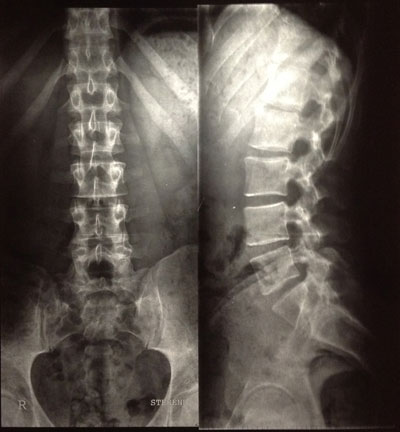

So, hier sind sie:

Was sagt ihr dazu? Welche Therapie ist zu empfehlen. Schroth zahlt die Kasse hier nicht. Irgendwelche Gedanken?

Die Skoliose ist ja hauptsächlich im Bereich der BWS, wie man erkennen kann.

- Dateianhänge

-

- BWS

- Foto-4.jpg (28.35 KiB) 14515 mal betrachtet

- LWS

- Foto-3.jpg (28.45 KiB) 14515 mal betrachtet

Kyphose (seitliche Aufnahme) müsste im grünen Bereich liegen

Skoliose, so ganz grob ca. um die 16 Grad.

LWS sieht doch ordentlich aus. Guter Abstand in den Bandscheibenfächern L 3,4,5

aber wenn dort eine Bandscheibe defekt sein soll, dann frage ich mich welche.

Weiter oben vermutlich bei L1, L2.

Aber das Becken steht irgendwie krumm da oder sieht das nur so aus, weil man

nicht alles sehen kann.

ich finde die Kyphose schon relativ deutlich im BWS-Bereich, die skoliotische Abweichung ebenfalls. Eventuell macht die Kombination von beidem die von Dir beschriebene Problematik. Aber das lässt sich via Internet nicht definitiv sagen. Dazu müsste man zum einen Dich "live" vor sich stehen haben und zum anderen die Bilder auf Folie in Originalgröße. An diesen kann man auch den Winkel ausmessen. Ausdrucke eignen sich zur Befundung nicht.

Es fällt eine Steilstellung der HWS, eine leichte Hyperkyphose und eine leichte Skoliose auf und mit Schroth könntest Du wahrscheinlich ganz gute Ergebnisse erzielen.